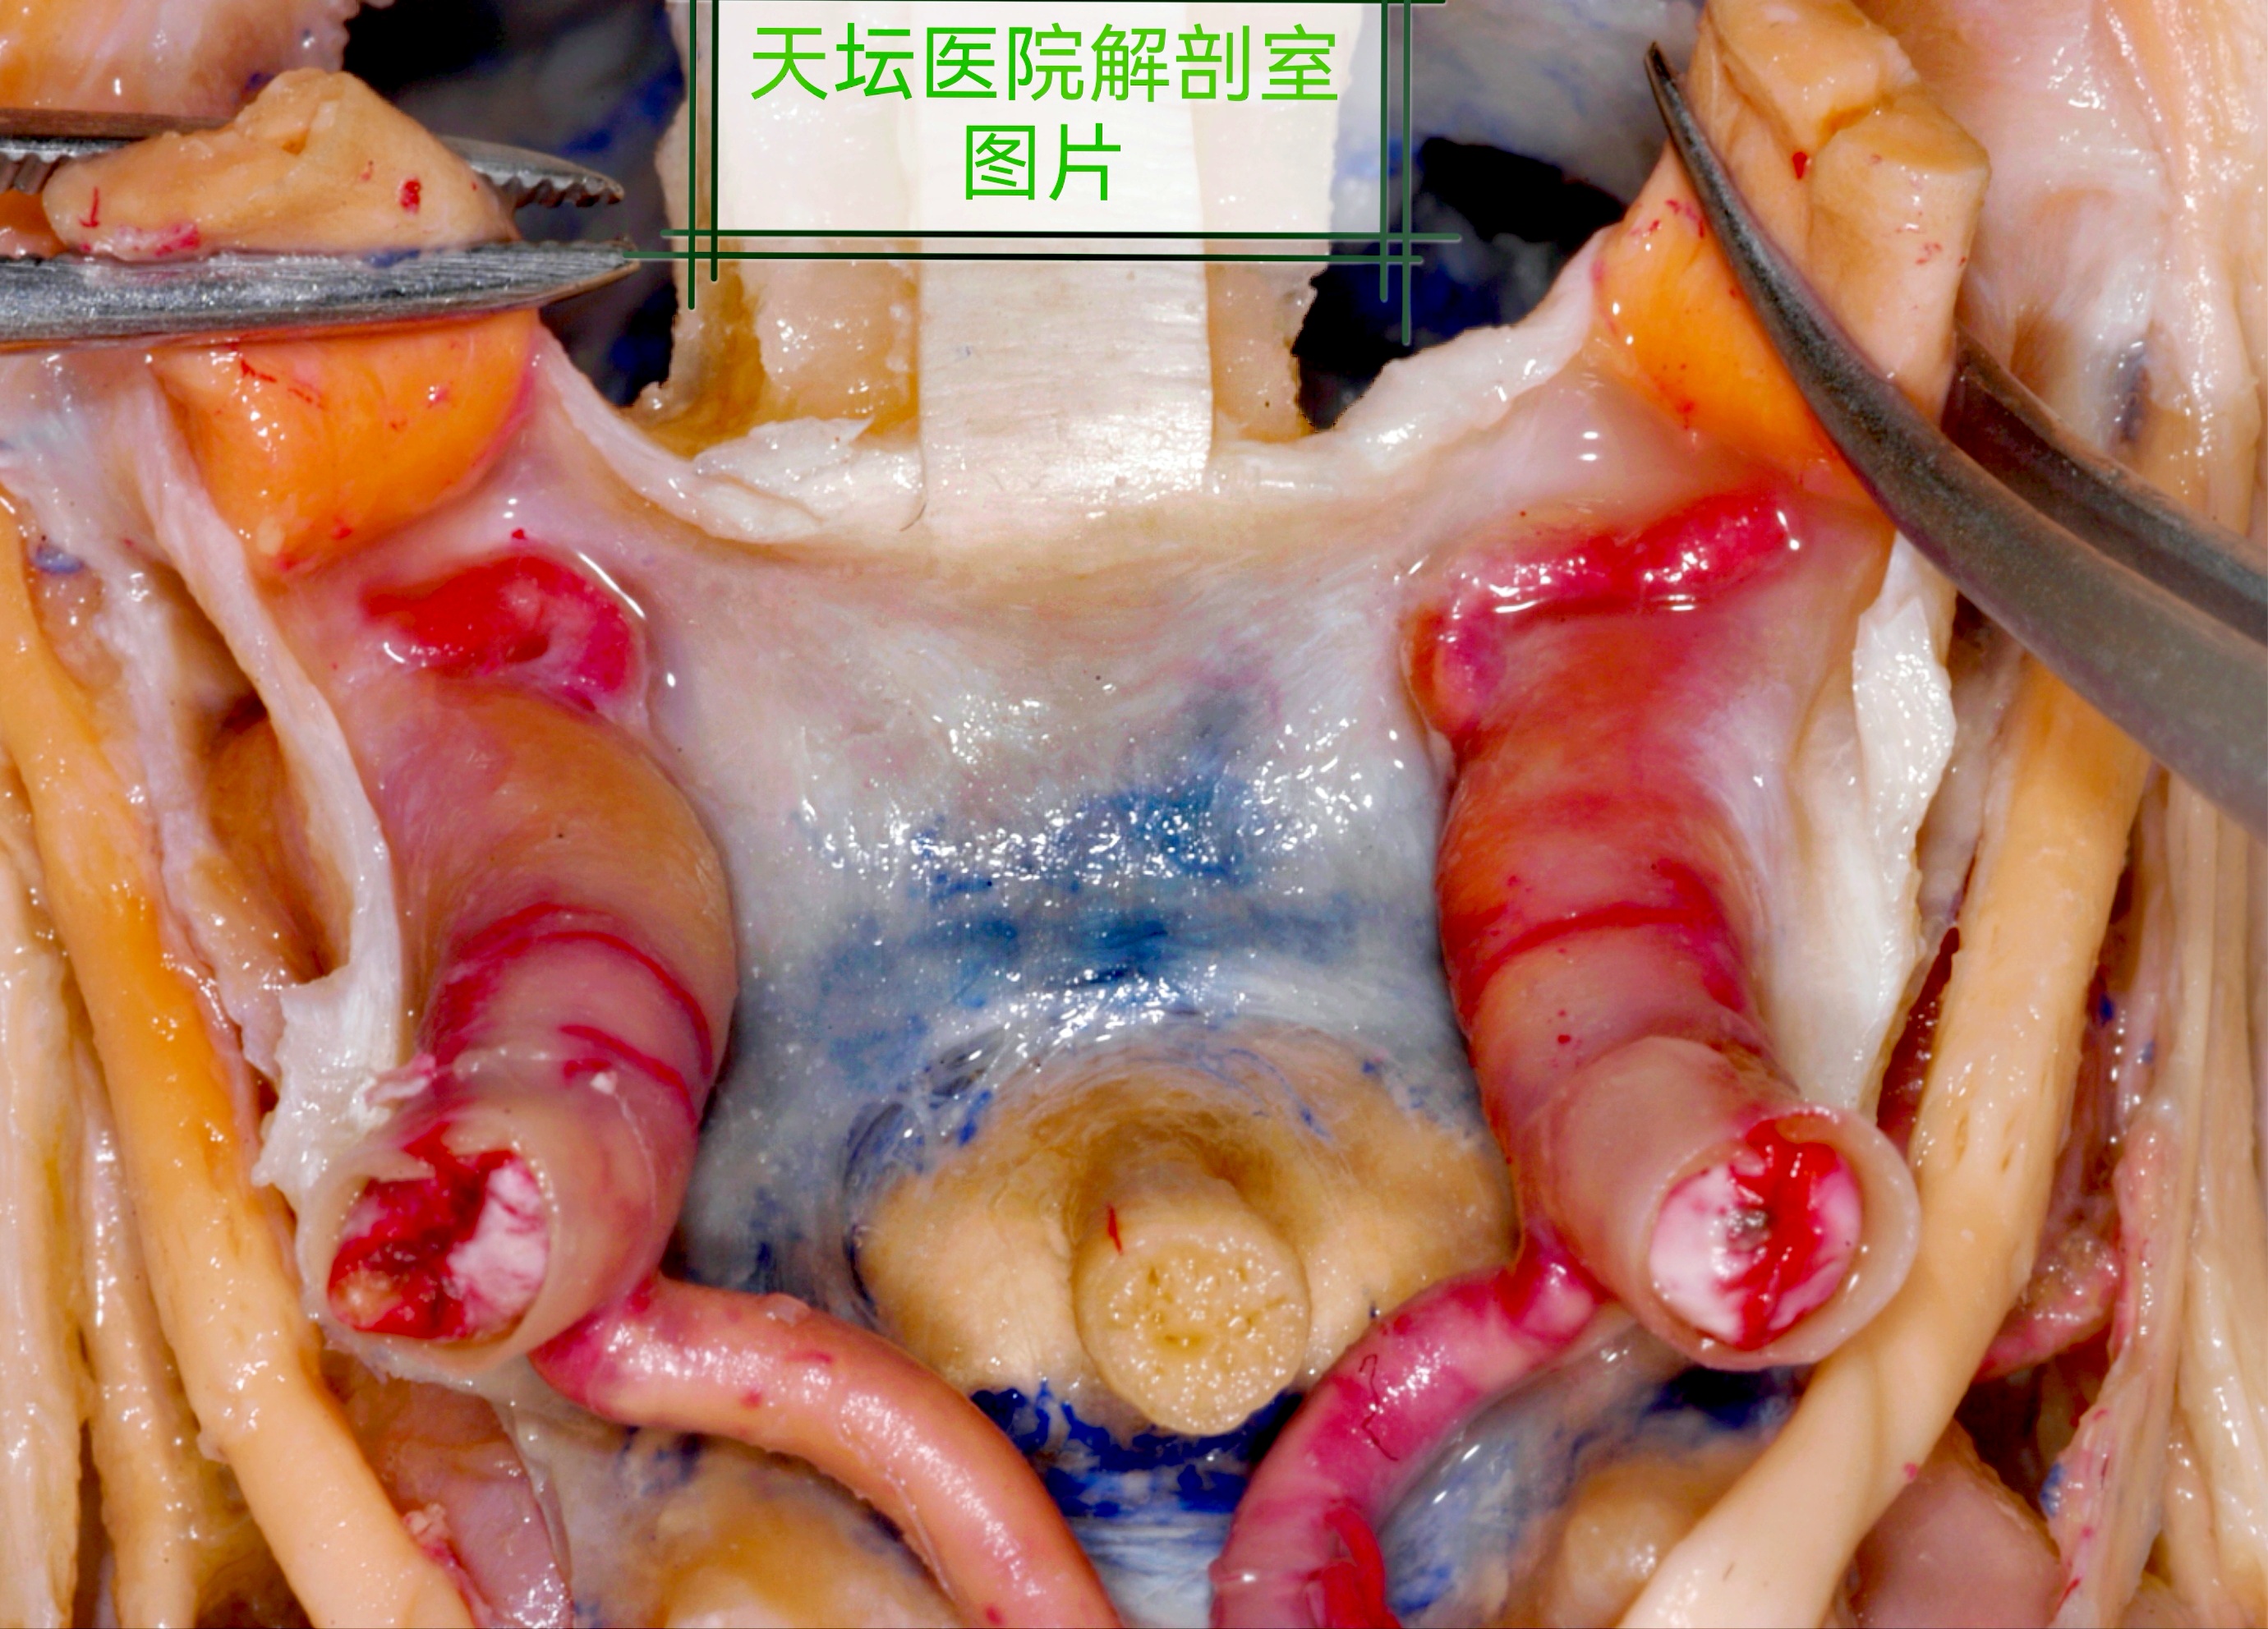

以下附几张天坛医院解剖室师兄们做的几张图片,方便

大家理解探查视神经管必要性。